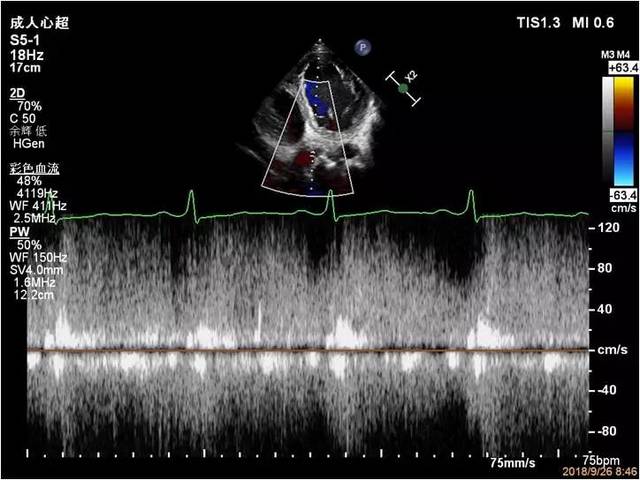

彩色多普勒显示收缩期二尖瓣口中等量反流